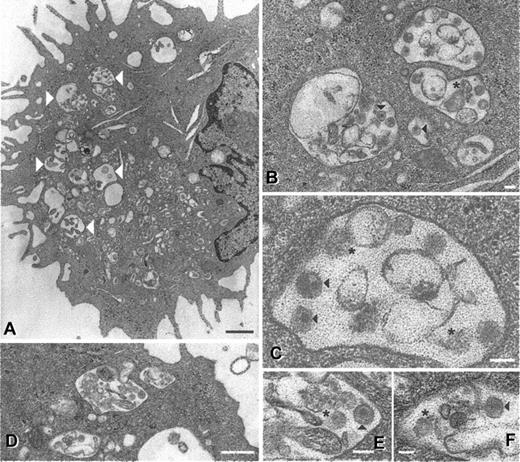

Electron microscopic analysis of 24-hour cultured cells revealed that residual viral proteins (and RNA) coincided with less intact virions being visible (Figure 5). Intact SIV particles were observed in large vacuoles within mature DCs (Figure 5A-C), although fewer than directly after initial uptake.22 Fragmented structures possibly representing cellular debris or degraded virions were also observed (Figure 5B-C, asterisks). Similar results were seen in DCs from 4 different donors, a total of 150 different cell profiles. In immature DCs, virus is located in smaller vesicles positioned just underneath the cell membrane immediately after exposure.22 Although more rare, SIV (Figure 5D-F) and HIV-1 (not shown) particles (both intact and possibly degraded) were still evident in 24-hour cultured immature DCs. These observations were made on DCs from 2 different donors, a total of 100 different cell profiles. Residual protein stains (Figure 4A-B) probably reflect intact virions as well as partially degraded virus seen by electron microscopy. The combination of protein detection, PCR, and electron microscopy indicates that virus captured by DCs is degraded with time and the fate of virus within the cell is readily influenced by external stimuli.

Ultrastructural appearance of SIV particles in DCs after 24 hours. Mature and immature DCs were pulsed with AT-2 SIV CP-mac for 2 hours, washed, and cultured for an additional 24 hours (immature DCs in GM-CSF and IL-4 and mature DCs in regular medium). At the 24-hour time point, cells were fixed and processed for electron microscopy as previously described.22 In mature DCs (A-C) large vacuoles (large white arrowheads) containing intact particles (black arrowheads) and cellular debris or possible degraded virions (asterisks) were observed. Similar virions (as well as debris or degraded viral particles) were observed in immature DCs (D-F), although at a markedly lower frequency. Magnifications and scale bars: (A) × 9000, 2 μm; (B) × 31 000, 100 nm; (C) × 81 000, 10 nm; (D) × 23 000, 0.5 μm; (E) × 60 000, 100 nm; (F) × 51 000, 100 nm. These images represent observations from 2 donors for the immature DCs and 4 donors for the mature DCs.